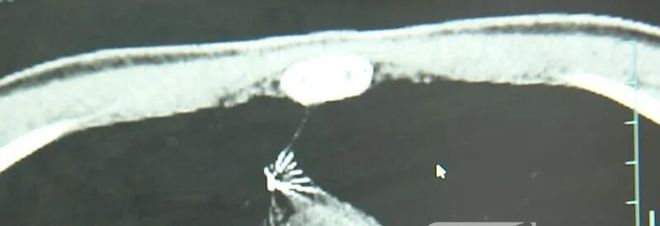

家人赶紧带着小陆到西湖大学医学院附属杭州市第一人民医院就医。接诊的心胸外科副主任冯兴表示:“这根针的尖锐部,正好指向他体内的一个大血管,边上是上腔静脉和胸主动脉,这根针稍有不慎,就有可能造成周边血管的损伤,甚至危及生命。”

近日,医院为小陆实施了mini单孔胸腔镜微创手术,切口仅2cm左右,成功将针完整取出。取出后发现,这根针长达5cm左右。